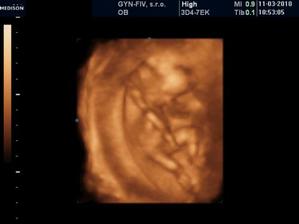

Náš chrústik - "Becky" 🙂